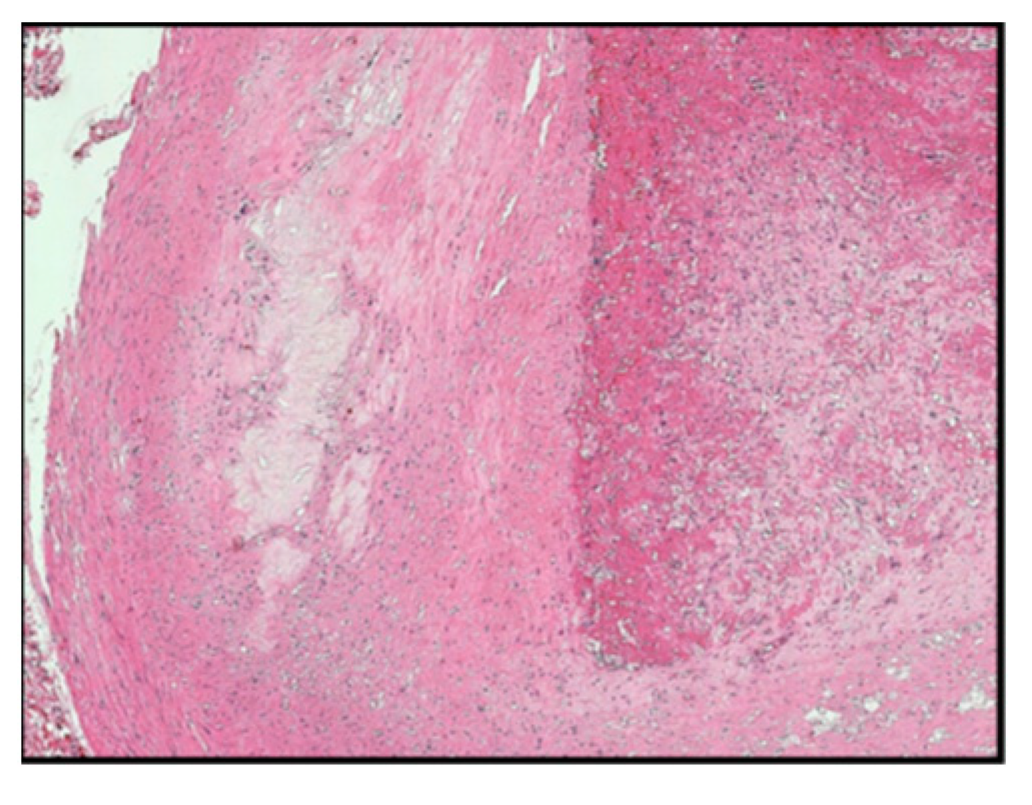

The histomorphology analysis of the arterial segments reveals atherosclerotic plaques in all of the examined cases. Three (5%) of the examined popliteal artery segments showed extracellular lipid deposits in the shape of cholesterol crystals (Figure 1). In total, 6 (10%) of the examined popliteal artery segments had fibro lipid plaques (Figure 2); 25 (41.6%) had calcified plaques (Figure 3); and in 14 (23.3%) of the examined segments, the intima was thickened and replaced by fibrotic connective tissue, and the quantity of lipids was minimal (Figure 4). Twelve (20%) of the segments presented complicated atherosclerotic plaques.

Figure 5. Complicated atheroma plaque with ulceration, fissure, thrombosis, and hemorrhage (type 6 according to Stary’s classification).